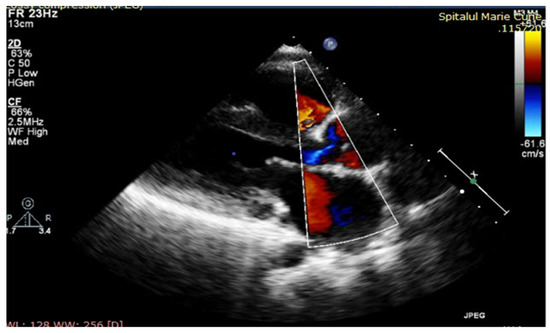

One year after surgery, our patient had a good cardiovascular status with good exercise tolerance and controlled BP on Furosemide and Captopril medication; muscle enzymes were still elevated after surgery (CK = 5156 UI/L, CKMB = 154 UI/L, ALT = 242 UI/L, AST = 147 UI/L, LDH = 649 UI/L), and the athletic deficit was aggravated progressively. The echocardiography showed moderate systolic biventricular dysfunction, with EF = 40%, minor regurgitation of neoaorta, good functionality of pulmonary homograft, mild mitral stenosis and a large residual coarctation (Figure 3).

Figure 3. TTE at one-year follow-up: minor regurgitation of neoaorta.